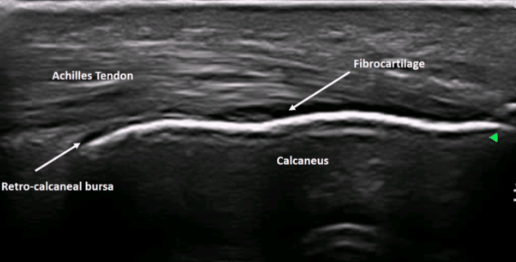

Achilles tendon

Strongest and thickest tendon in the body

Attachments

Proximal - gastrocnemius and soleus muscles

Distal - calcaneus (heel bone)

Normal US appearance of Achilles tendon

Retrocalcaneal bursitis